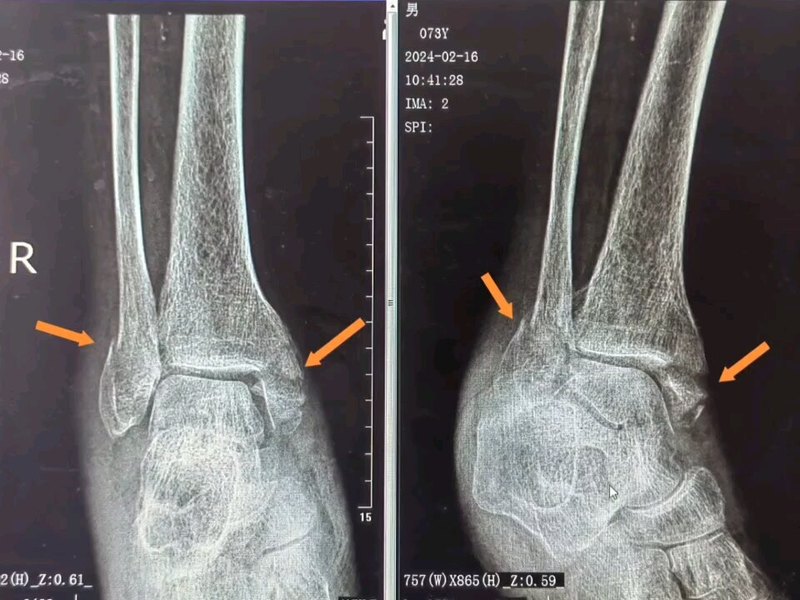

患者,女,33歲,因“騎電動(dòng)自行車車禍傷致左踝關(guān)節(jié)腫脹畸形1小時(shí)”入院,查體:內(nèi)踝前皮膚損傷(圖1),踝關(guān)節(jié)壓痛(+)。CT提示:左側(cè)內(nèi)踝骨折(圖2)。(病人車禍傷,基本醫(yī)療保險(xiǎn)不予報(bào)銷,自己購(gòu)買(mǎi)的商業(yè)保險(xiǎn)報(bào)銷)視頻1:術(shù)后3個(gè)月隨訪1.術(shù)后患者不用二次手術(shù)取內(nèi)固定物2.第二次取內(nèi)固定物的費(fèi)用與可吸收螺釘?shù)馁M(fèi)用相比,明顯少很多3.內(nèi)踝松質(zhì)骨血運(yùn)豐富,骨折愈合快,更易于可吸收螺釘?shù)氖褂?/p>